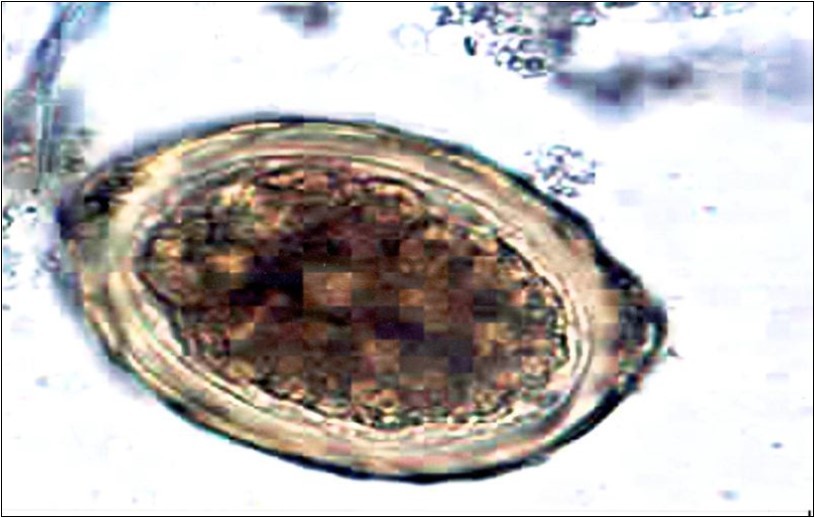

Figure 4.Schistosoma mansoni egg